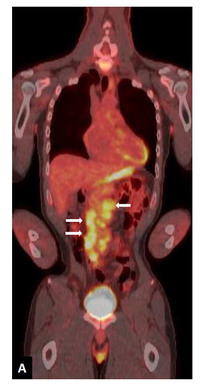

Histiocytic sarcoma-PET

See reference case of histiocytic sarcoma for details.